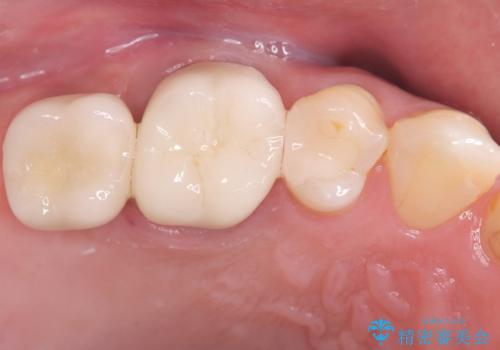

まず、右上6・右下6の根管治療を再度行い、根の状態をしっかり整えた上で、セラミッククラウンを装着しました。さらに、欠損していた右上7・右下7にはインプラントを埋入し、セラミッククラウンを装着。治療後は、「奥歯でしっかり噛めるようになり、不安なく食事ができるようになった」と患者様にも大変ご満足いただきました。